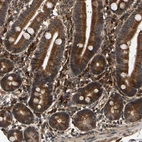

Immunohistochemical staining of human duodenum shows strong cytoplasmic positivity in glandular cells.